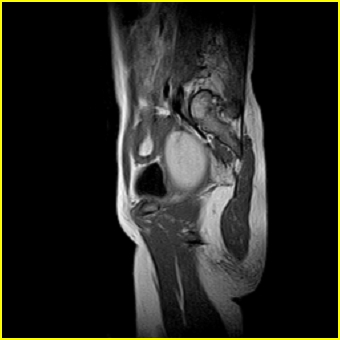

女、15岁、下腹疼痛2天,排尿困难1天。查体:处女膜闭锁,距处女膜约4至5cm处扪及一约5cm直径的圆形包块,张力较高,触痛明显、欠活动。b超提示子宫增大伴宫内增强回声团。

更正影像意见:阴道积血。

处女膜闭锁,阴道积血,子宫积血.

处女膜闭锁,伴子宫及阴道积血.